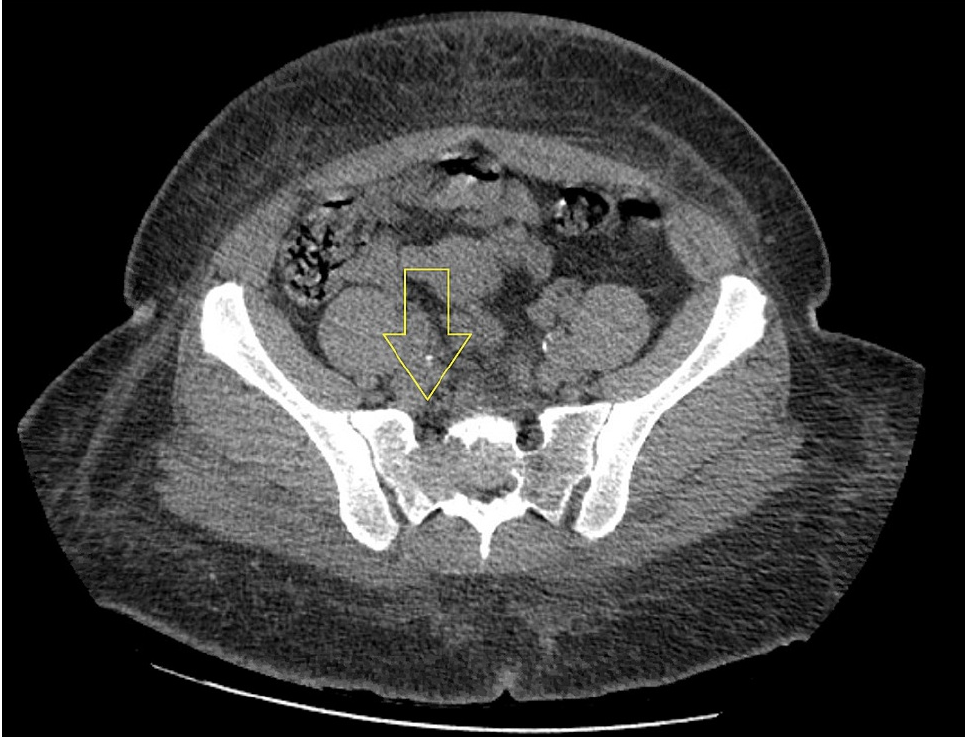

Tomografía Computarizada (TC)

- Evalúa mejor el patrón trabeculado y la integridad cortical.

- ¿Puede mostrar matriz osteoide? No. Si hay, pensar en osteosarcoma.

- Útil para biopsia guiada y planificación quirúrgica.

Estudios de imagen — Hallazgos y protocolo 2026

- Lesión lítica pura, bien o mal definida según agresividad.

- Patrón expansivo: Puede simular "pompa de jabón" o panal de abeja (trabeculado grosero).

- Cortical: Adelgazada, puede estar expandida. Destrucción parcial en lesiones agresivas.

- Reacción perióstica: Ausente en la mayoría de casos (clave diferencial con sarcoma de Ewing u osteosarcoma).

- Masa de partes blandas: Infrecuente.